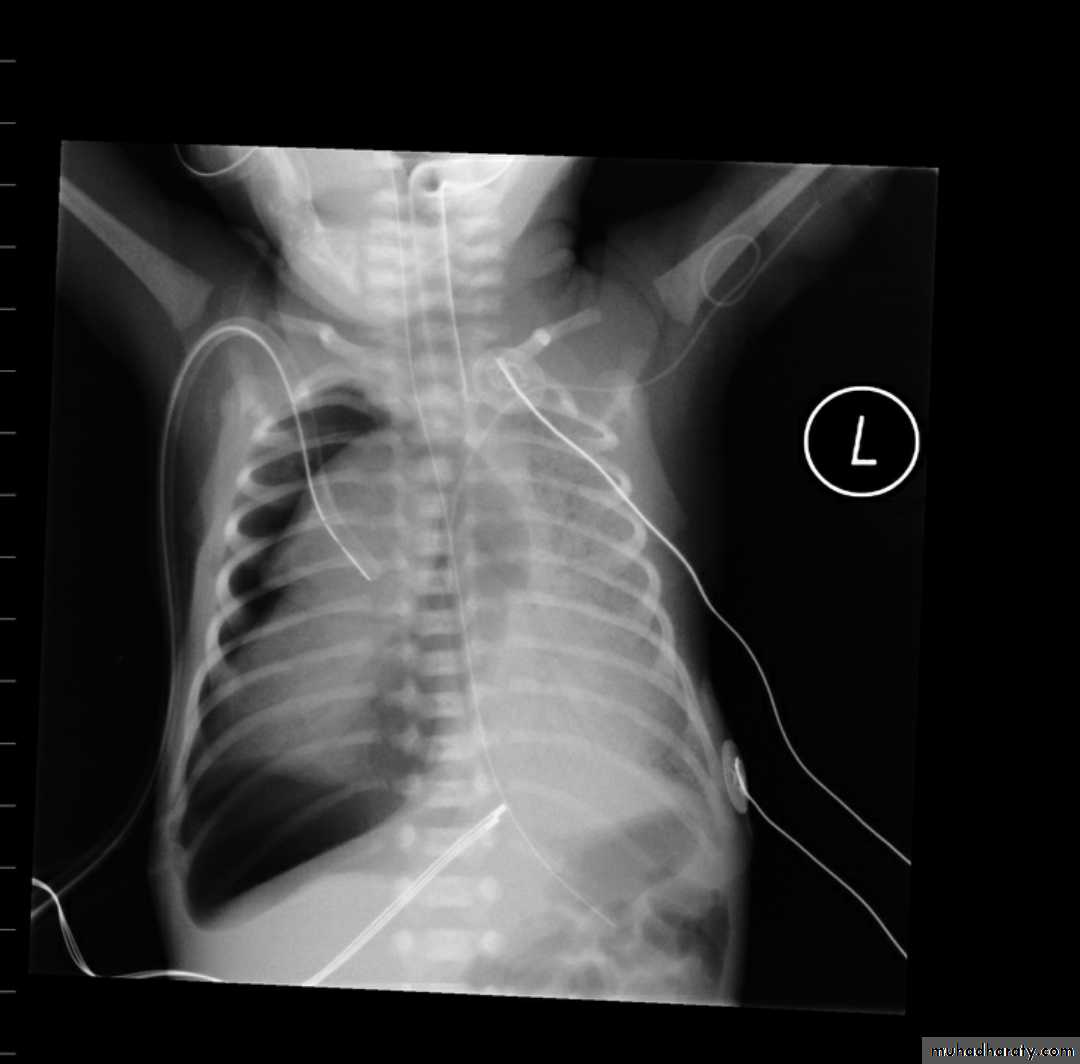

Tension pneumothorax

56.tension pneumothorax left sided aspect

57. tension pneumothorax right sided aspect